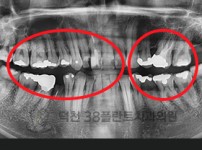

치료전후